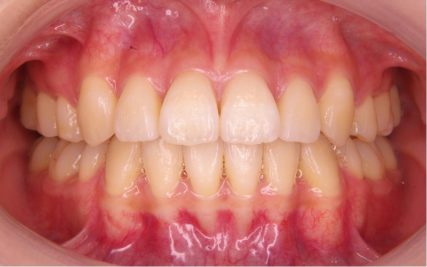

でこぼこ/20代女性

- 不正咬合/叢生(でこぼこ)

- 治療前

- 上下とも前歯のスペース不足が認められた。歯のサイズと顎の幅とのバランスが不調和な事が原因の1つとして考えられる。

- 治療後

- 前歯部のでこぼこが解消され、正常咬合を獲得する事が出来た。又、歯科矯正用アンカースクリューを用いる事で抜歯スペースを有効に利用できた。